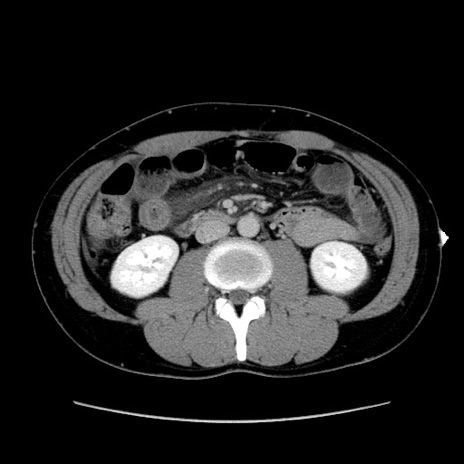

症例36(横断像)

【症例】20歳代 男性

【主訴】心窩部痛

【現病歴】今朝より上腹部痛あり。一旦軽快していたが再度出現したため救急要請。昨日夕に白身の魚を含む刺身を食べた。

【身体所見】BP 136/89mmHg、HR 74/min、BT 37.0℃、腹部:膨満、軟、心窩部に圧痛あり。反跳痛なし、筋性防御なし、腸雑音やや亢進あり。

【データ】WBC 17700、CRP 0.48